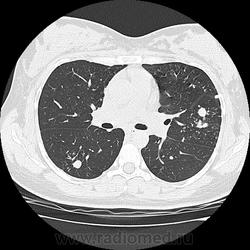

- https://radiomed.ru/sites/default/files/styles/case_slider_image/public/user/19376/img-0001-00042.jpg?itok=2lfc8wWs

- https://radiomed.ru/sites/default/files/styles/case_slider_image/public/user/19376/img-0001-00052.jpg?itok=YRoMhMgw

- https://radiomed.ru/sites/default/files/styles/case_slider_image/public/user/19376/img-0001-00056_0.jpg?itok=nxleffCp

- https://radiomed.ru/sites/default/files/styles/case_slider_image/public/user/19376/img-0001-00061.jpg?itok=rsGqsfJo

- https://radiomed.ru/sites/default/files/styles/case_slider_image/public/user/19376/img-0001-00066.jpg?itok=jCurkizB